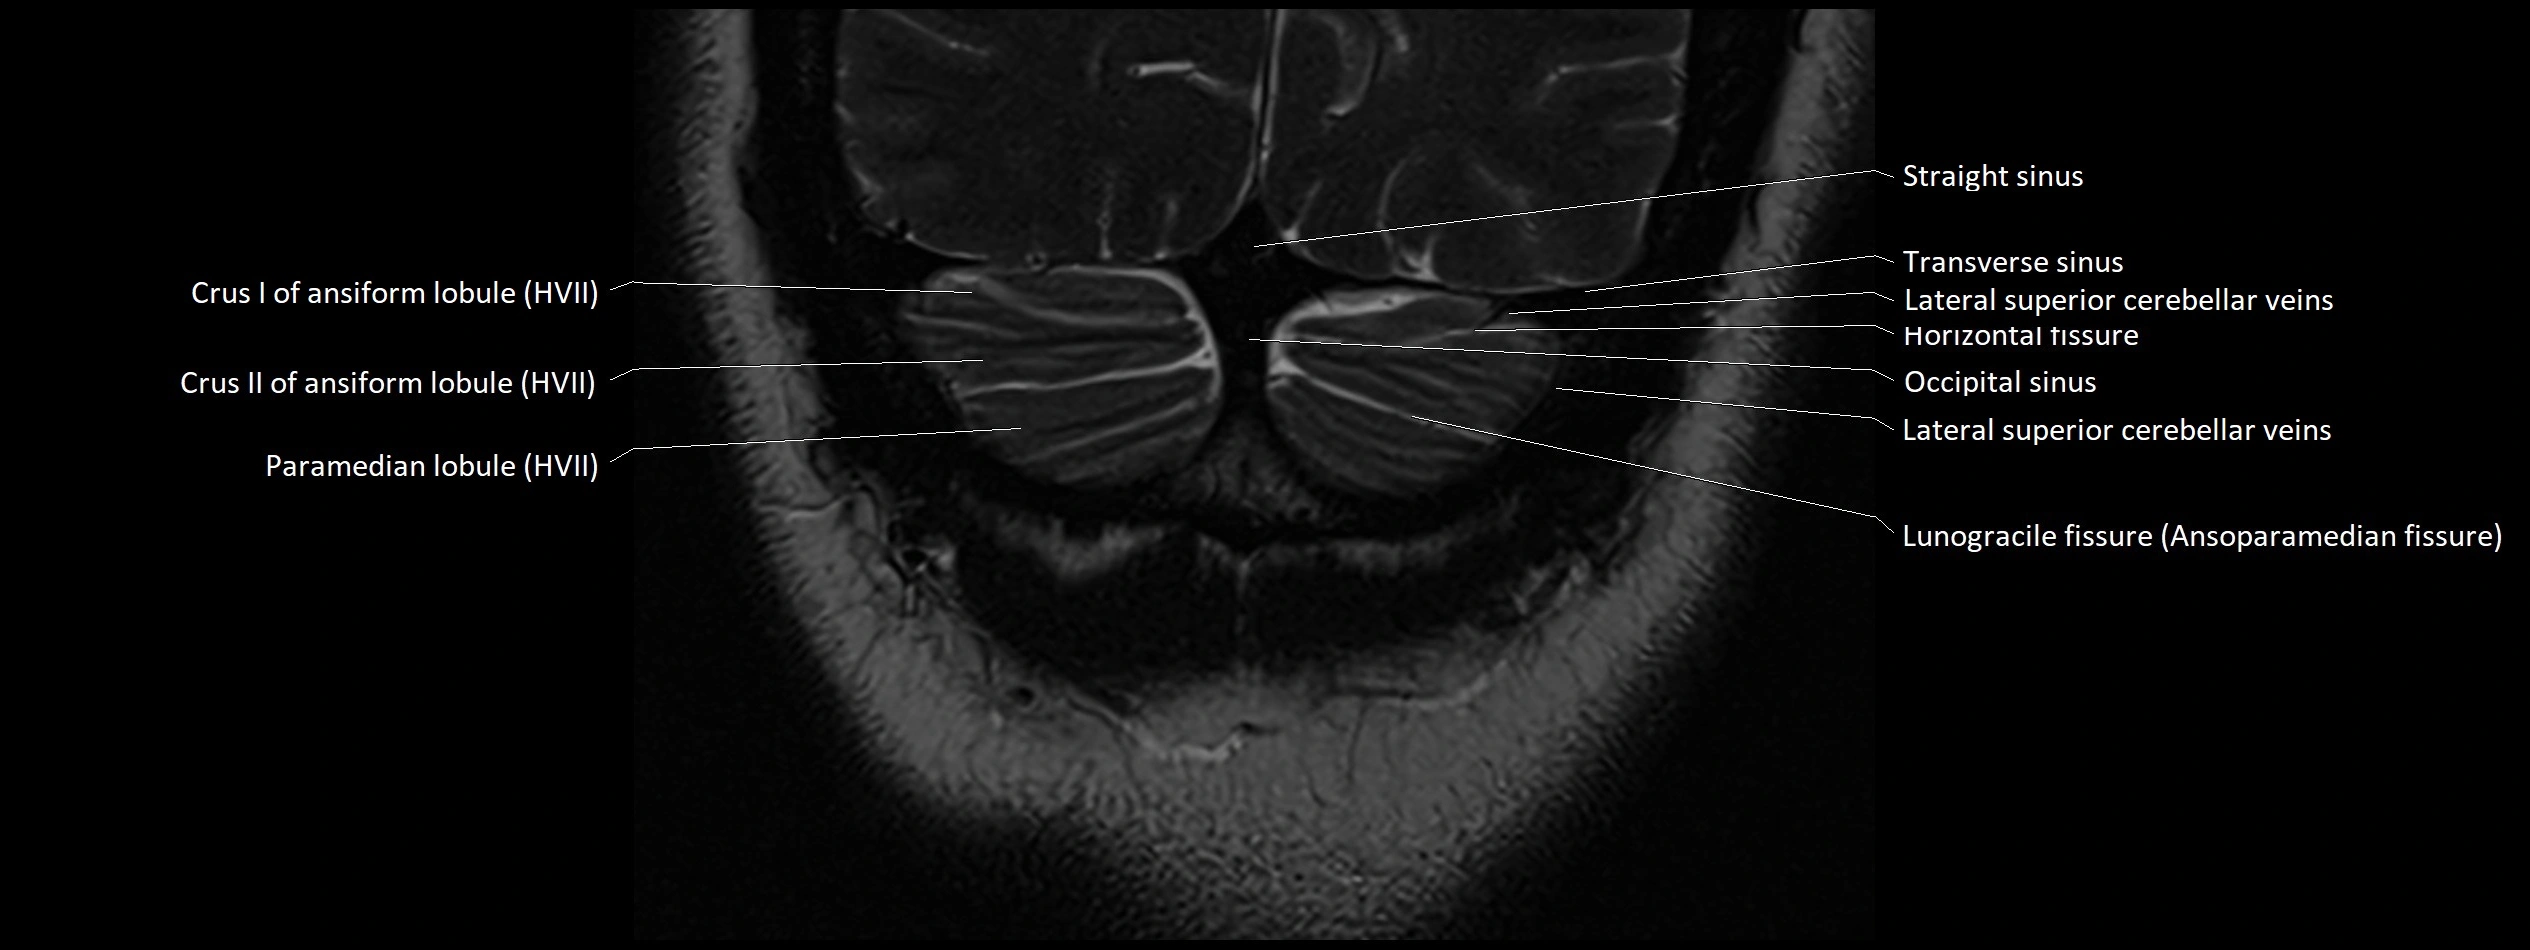

- Crus I of ansiform lobule of cerebellum

- Crus II of ansiform lobule of cerebellum

- Horizontal fissure (cerebellum)

- Lunogracle fissure

- Lunogranicile fissure of cerebellum

- Paramedian lobule

- Paramedian lobule (HVII) of cerebellum

- Transverse sinus